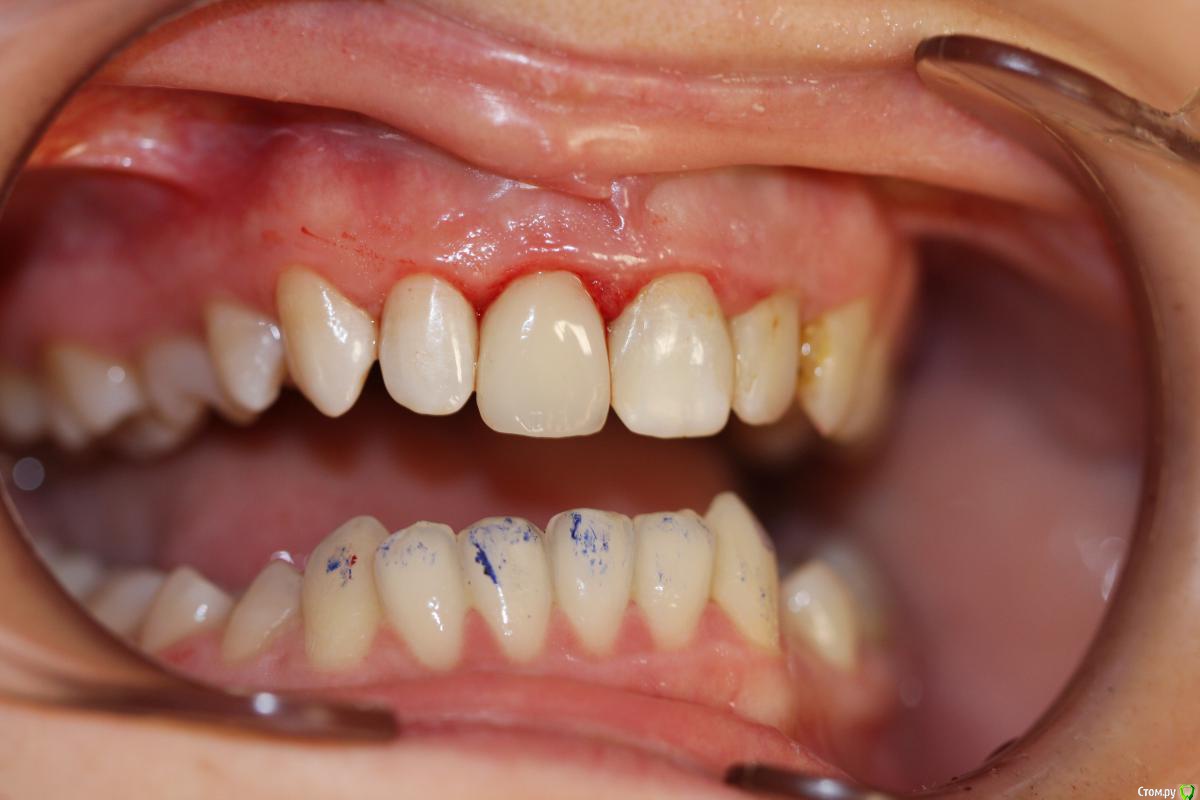

skeettrap Опубликовано 23 марта, 2016 Автор Поделиться Опубликовано 23 марта, 2016 Зуб ушёл ниже десны. Это сто проц. удаление, имплант и коронка. По мне так пациент переплатил. К импланту всё равно придёт. Спор.. из серии: Доедет, ли колесо до Санкт Петербурга??? По показаниям .. здесь ортопедия.Из мнений хирурга-имплантолога и ортопеда разделю мнение Юрия (земляки все-же), и уважения к нему больше (исходя из выставленных работ), а останусь со своим. Ссылка на комментарий

skeettrap Опубликовано 23 марта, 2016 Автор Поделиться Опубликовано 23 марта, 2016 Зуб ушёл ниже десны. Это сто проц. удаление, имплант и коронка. По мне так пациент переплатил. К импланту всё равно придёт.Хороши сомнения.Я говорю о том, что я это иногда делаю и это работает. Если у Вас опыт такой, что в течениеН-го времени Вы СВОИ(!) работы подобного рода заменили на имплантаты в 100% случаев, то Вы действительно отличный имплантолог, но здесь раздел ТЕРАПИЯ. Ссылка на комментарий

Л Ю С Я Опубликовано 24 марта, 2016 Поделиться Опубликовано 24 марта, 2016 Тоже видела работы без штифта в дент- арте 90 годов. Только начала тогда работать . Побаивалась как- то, все равно анкер клеила. Зато коллега, ярый фанат Сергея Владимировича, делал и такие конструкции, и полную резекцию дентина депульпированный зубов, и мостов мерелиндских понаделал всяких. По поводу темы: бюджетная временная конструкция. Бывают ситуации всякие. Хотя видно, что доктор старался и неплохо владеет техникой прямой реставрации. Если мне попадаются мои пациенты с такими работами 5-10 летней давности выжившие, особенно если у пациента проблемы с гигиеной,хочется спрятать глаза, не нравиться категорически,чувствуешь себя идиоткой. 1 Ссылка на комментарий